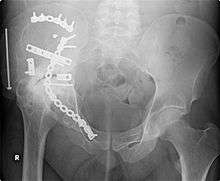

Orthopedic surgery or orthopedics (alternatively spelled orthopaedic surgery and orthopaedics) is the branch of surgery concerned with conditions involving the musculoskeletal system. Orthopedic surgeons use both surgical and nonsurgical means to treat musculoskeletal trauma, spine diseases, sports injuries, degenerative diseases, infections, tumors, and congenital disorders.